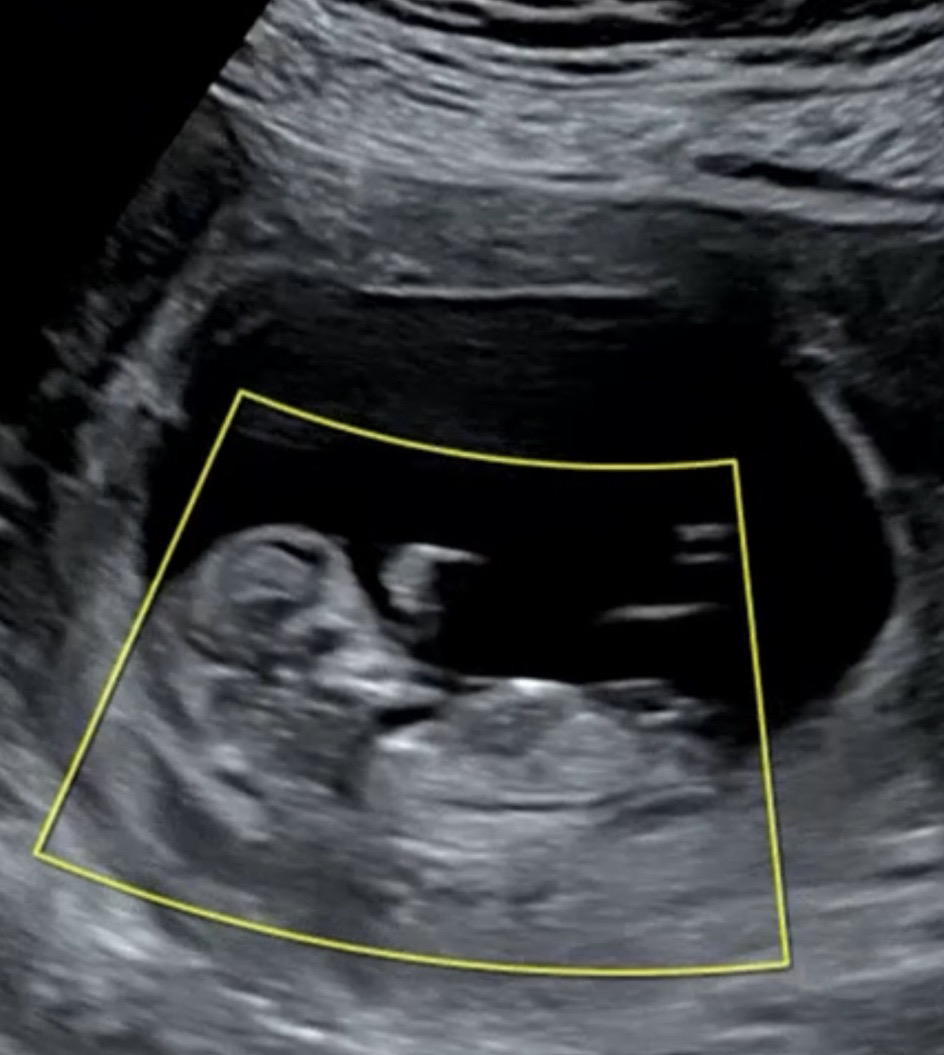

각도법 고수님들 함 봐주시면 감사하겠습니다!!

12주예용!! 성별이 뭘까여???

조심스럽게 딸이요..!